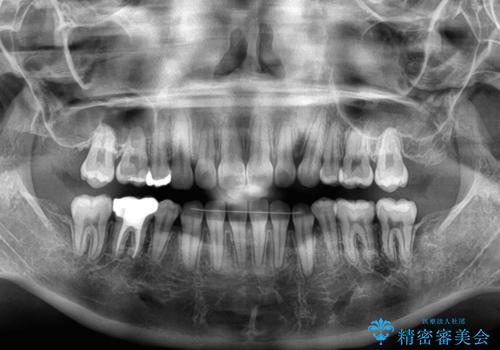

レントゲン写真の分析結果からは、それほど口元が突出しているという結果にはなりませんでした。

しかしながら、唇を閉じたときに口元に緊張感があり、そのまま叢生を解消すると横顔が突出した印象になる可能性が高かったため、上下左右の小臼歯4本を抜歯して、ワイヤー装置にて矯正治療を行うこととしました。